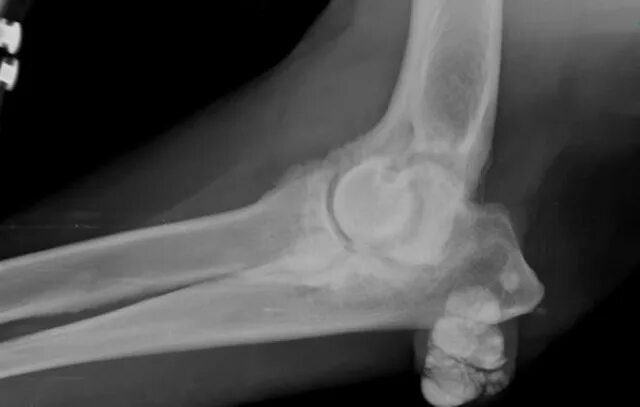

Отложение кальция